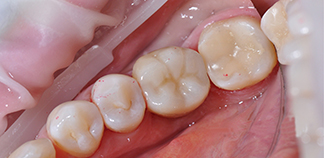

Результаты лечения пациентов

До лечения

Жалобы на отсутствие зубов.

Как лечили

Установлены импланты и зафиксированы постоянные коронки.

Лечащий врач

КИСЕЛЕВ Кирилл Эдуардович